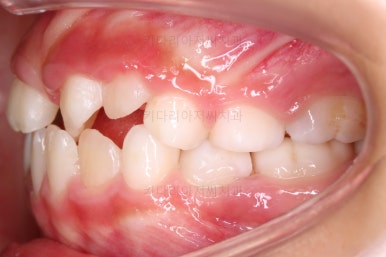

부산어린이반대교합 초진 시, 치열의 모습이에요.

앞니가 거꾸로 물려있고(아래 앞니가 위 앞니보다 앞으로 튀어나간 상황) 삐뚤어 있어요.

영구치 앞니가 거꾸로 물려있으면 발견 즉시 개선해줘야 합니다.

다른 치아는 삐뚤던 말던 거꾸로 물리던 말던 영구치 앞니가 거꾸로 나와있다면 무조건 서두르셔야 합니다.

거꾸로 물린 앞니가 아래턱을 앞으로 혹은 측방으로 밀어내어 없던 주걱턱도 생기고 없던 비대칭도 생긴답니다.